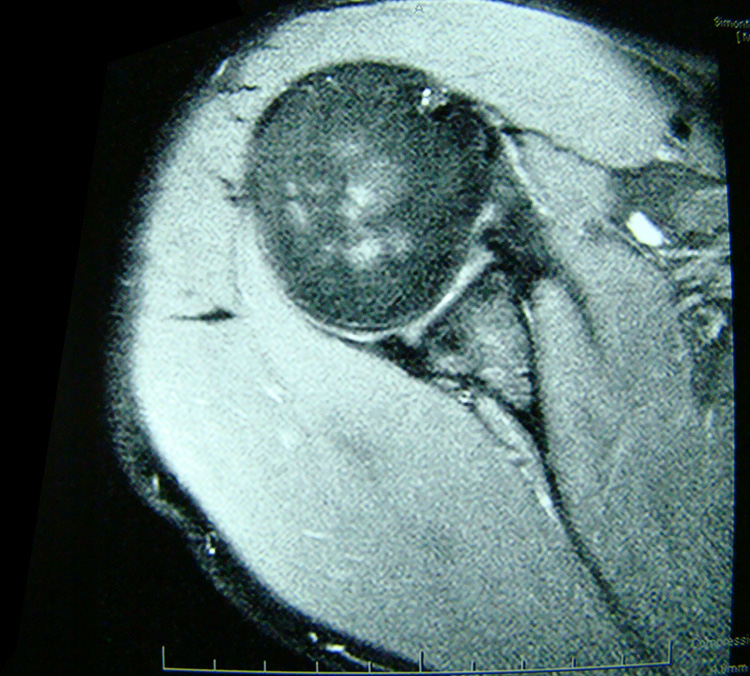

This patient presented with shoulder pain that interfered with work and exercise. The visible fluid-filled cysts on the “Before" MRIs are from chronically injured rotator cuff tendon roots.

The patient underwent treatments of a highly specialized fine-needling technique pioneered by Dr. Tallman.The follow-up MRI was done 2 months after his 6th treatment. He was released with a pain-free, full range of motion with unrestricted activities.